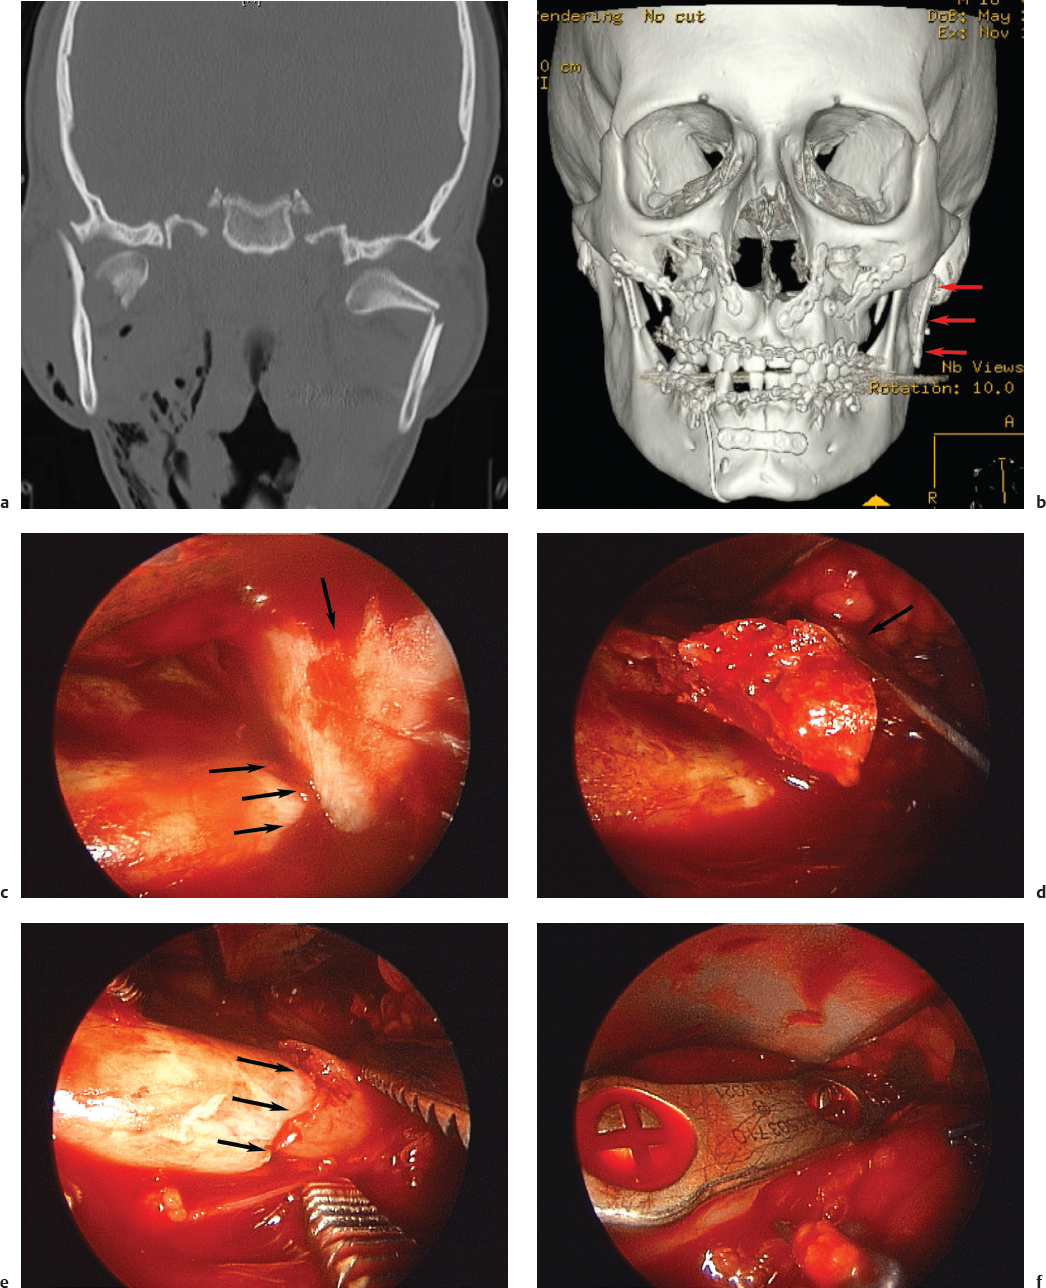

ORIF may prevent vertical height loss, facial asymmetry, malocclusion, deviation on mouth opening, and chronic temporomandibular joint pain in select patients; however, the surgeon must weigh the merits of ORIF against increased risks of facial nerve injury and visible facial scarring ( Fig. 65.5 ). 17 Endoscopic repair of subcondylar fractures is an alternative to traditional open approaches for surgeons trained in this technique. Endoscopy eliminates the need for a significant external incision and decreases the risk of facial nerve injury while still allowing for open reduction and plating of the fracture ( Fig. 65.6 ). Unfortunately, the equipment and surgical expertise required to effectively execute endoscopic repairs are not always available. 15